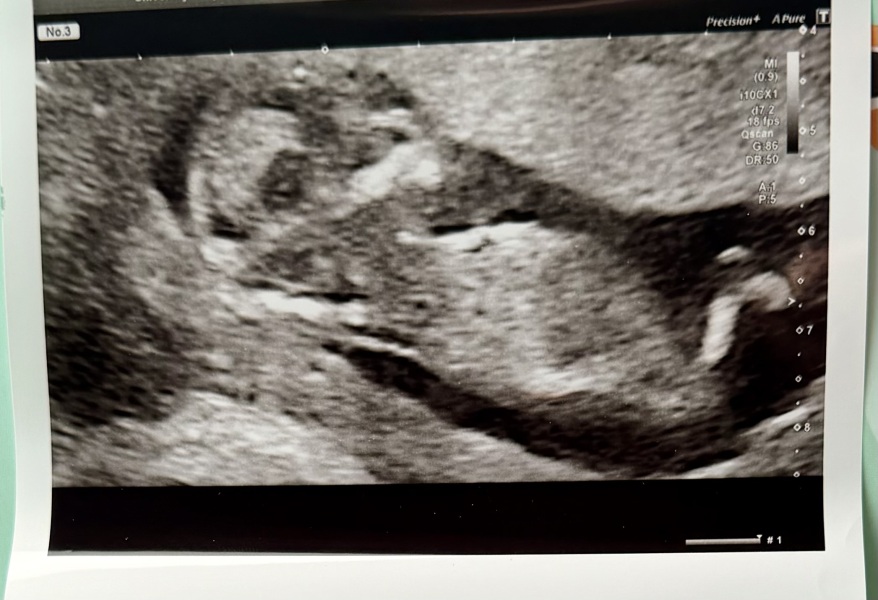

Can anyone see the nub from this dating scan image?

We had our dating scan yesterday for our 3rd baby. The scan was tricky due to baby’s position apparently but I’m just wondering if anybody can see the nub on this picture?

I have no idea what I’m looking at but would love to hear others opinions.